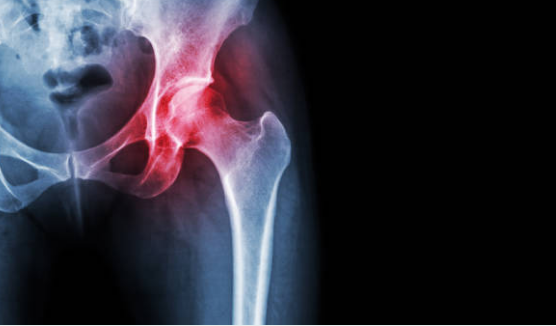

고관절 통증 원인

고관절 통증의 원인은 다양할 수 있습니다.

퇴행성 관절염: 나이가 들면서 고관절의 연골이 마모되어 통증이 발생할 수 있습니다.

비만: 과체중으로 인해 고관절에 가해지는 부담이 커져 통증이 생길 수 있습니다.

외상: 교통사고나 운동 중 부상으로 인해 고관절에 손상이 발생할 수 있습니다.

잘못된 자세: 오랜 시간 동안 잘못된 자세로 앉아 있거나 서 있는 습관이 고관절 통증을 유발할 수 있습니다.

선천성 질환: 선천적으로 고관절에 문제가 있는 경우 통증이 발생할 수 있습니다.

감염: 고관절 주변 조직에 감염이 발생하면 통증이 생길 수 있습니다.

고관절 통증이 지속되거나 심해진다면 전문의와 상담하여 정확한 진단과 치료를 받는 것이 중요합니다.